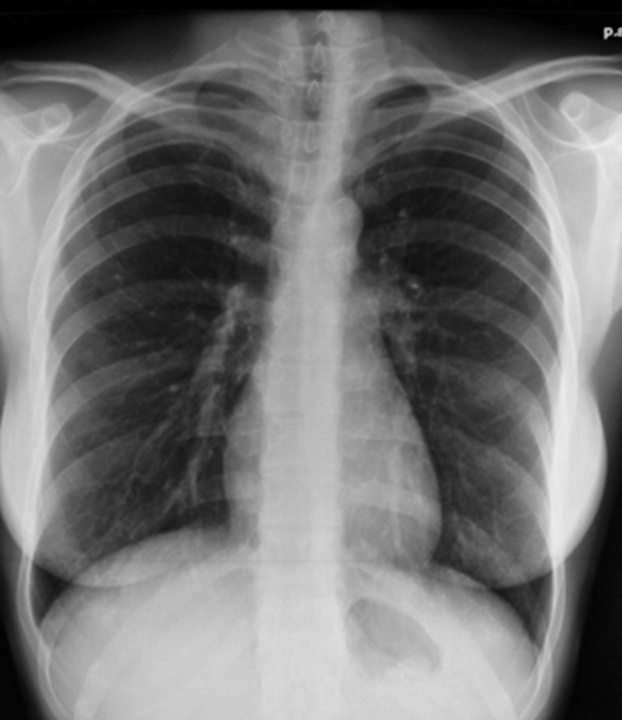

ECR 2013 Vascular redistribution pattern. PAChest radiograph of a patient with mitral

Stage I Redistribution In a normal chest film with GrepMed

Connaître les différents tableaux liés aux processus ischémiques en radiographie, TDM, IRM, échographie et médecine nucléaire.. (dilatation et redistribution vasculaire vers les sommets), la diffusion du liquide dans l'interstitium pulmonaire (syndrome interstitiel), voire une diffusion du liquide dans les alvéoles (syndrome.. stade 1 : redistribution vasculaire vers les sommets qui deviennent aussi denses que les bases stade 2 : oedème interstitiel avec plusieurs aspects : -lignes de Kerley correspondant à un oedème des cloisons septales. Les mieux visibles sont les lignes B, petites lignes horizontales, fines et courtes siégeant à la base des champs pulmonaires.